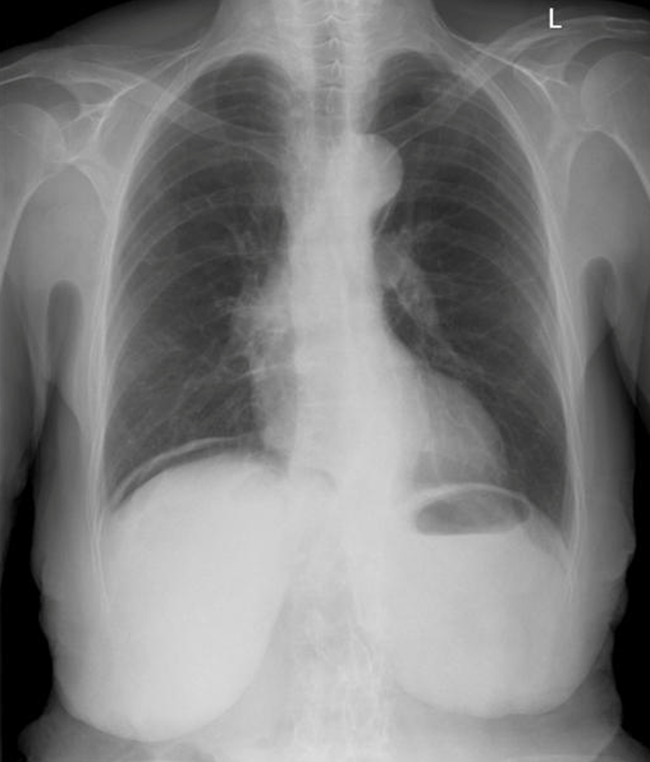

What is your most likely diagnosis?

Finding is displayed in this image?

How will you manage this patient?

!Erect! CXR for perforation -> pneumoperitoneum!

Perforated duodenal/gastric ulcer (duodenal more common) - Most likely diagnosis